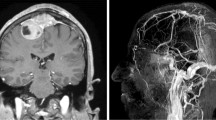

According to intraoperative findings, 40% (10/25) of the aneurysms were intracavernous, 8% (2/25) transitional and 52% (13/25) intradural, whereas MRI scans indicated 44.4% (11/25) of the aneurysms as intracavernous, 4% (1/25) as transitional and 52% (13/25) as intradural (Tables 1 and 3). Examples of intracavernous, transitional and intradural aneurysms are presented in Figs. 1, 2, 3, 4. Figure 5 presents a transitional aneurysm previously classified as intracavernous on MRI.

Cerebral digital subtraction angiography (DSA) of intradural aneurysm #22 (see Table 1) showing anteroposterior (panel A) and profile (panel B) views. Note the medial and inferior projection of the aneurysm (white arrows). Coronal T2-weighted magnetic resonance imaging (MRI) scans with a 3D fast spin-echo sequence showing anterior to posterior views of the anatomoradiological markers of the paraclinoid region and intradural aneurysm #22 (panels C–F). Note the hyper-intense signal from the cerebrospinal fluid (white arrows). In panel G–I, three-dimensional time-of-flight (TOF) magnetic resonance angiography was employed to enhance the view of the aneurysm (white arrows)

Cerebral digital subtraction angiography (DSA) of intracavernous aneurysm #19 (see Table 1) showing anteroposterior (panels A and C) and profile (panels B and D) views. Note the medial projection of the aneurysm (white arrows). Coronal T2-weighted magnetic resonance imaging (MRI) scans with a 3D fast spin-echo sequence showing anterior to posterior views of the anatomoradiological markers of the paraclinoid region and intracavernous aneurysm #19 (panels E–H). Note the hyper-intense signal from the cerebrospinal fluid around the distal dural ring and no contact between CSF and the aneurysm (arrow heads)